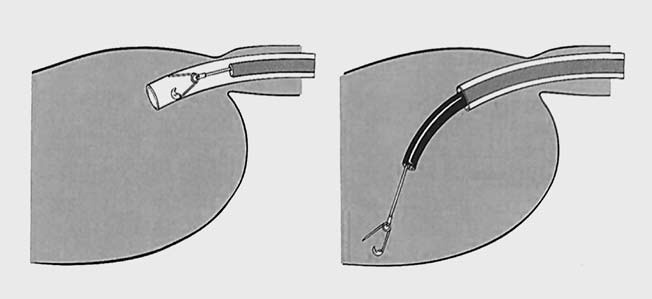

Endoskopické vyšetření horního zažívacího traktu u dětí je třeba provést v celkové anestezii, v případě CT se zajištěním dýchacích cest endotracheální intubací, abychom zabránili vdechnutí (aspiraci). Výkon by měl být prováděn na dobře vybaveném endoskopickém pracovišti. Vedle zkušeného endoskopisty a anesteziologa tu hraje velkou roli i asistence zkušené endoskopické sestry. K extrakci CT se používají různá akcesoria - kličky, kleště, košíky, tripody (obr. 2-4). V případě extrakce ostrých předmětů je vhodné použít overtube (kryt, do kterého je ostré CT vzato, aby nedošlo k poranění stěn zažívacího traktu) (obr. 5).